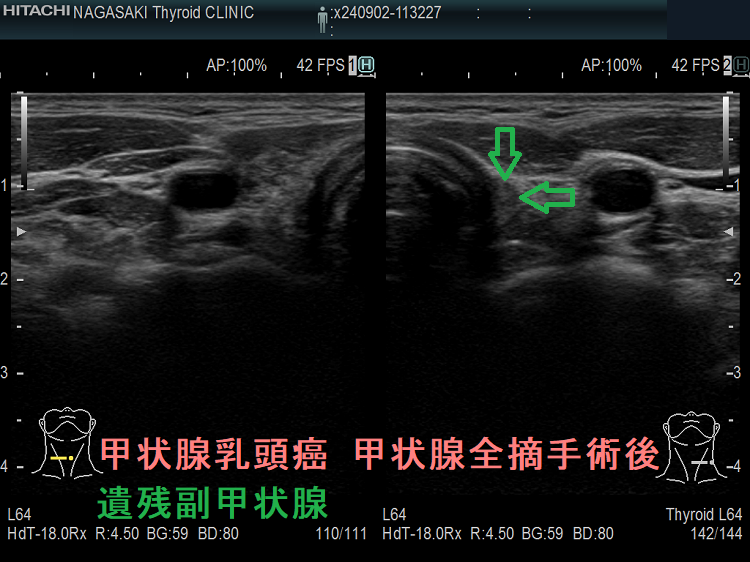

- 甲状腺摘術後、TSH 抑制療法;バセドウ病/甲状腺腫瘍で甲状腺切除と同時に副甲状腺も取ってしまった場合、取らずに温存した場合でも副甲状腺への血管を傷つけた場合

- 頭頚部癌、サルコイドーシスで頚部手術後・放射線照射後の副甲状腺損傷・副甲状腺切除

- 甲状腺癌、頭頚部癌の副甲状腺浸潤

- 甲状腺全摘術時、副甲状腺も1-4腺を同時切除、あるいは切除しなくても栄養血管を損傷

- 甲状腺亜全摘術時、副甲状腺を数腺温存したつもりが、栄養血管を損傷

- 術後副甲状腺機能低下症による低カルシウム血症;術直後のみならず、10年~30年以上して著明な低カルシウム血症で発症する事もある(日腎会誌 2012;54(1):40-47.)(J Clin Diagn Res. 2017 Feb; 11(2): OD07–OD09.)。